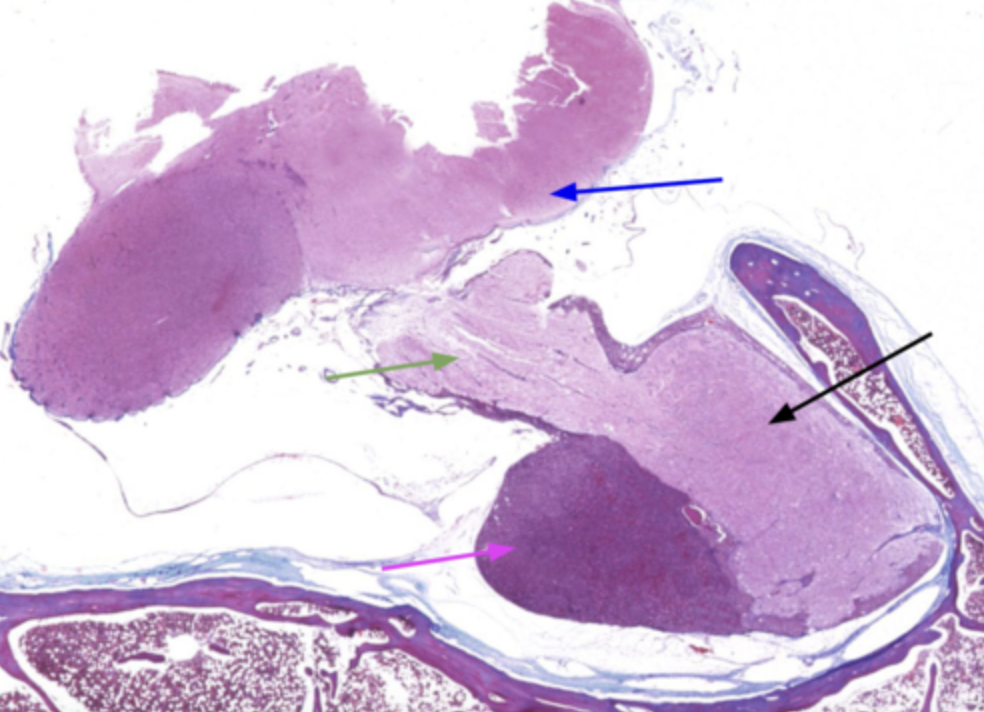

What is the magenta arrow pointing to?

adenohypophysis

What is the black arrow pointing to?

Neurohypophysis

The adenohypophysis is what in color when compared to the neurohypophysis

Darker in color

What is the green arrow?

Infundibulum

What is the blue arrow?

Hypothalamus

Why is the adenohypophysis darker than the neurohypophysis?

Because it has a variety of cell classes responsible for producing many hormones. It also contains a lot more blood vessels than the neurohypophysis

Why is the neurohypophysis lighter?

Because it’s primarliy made up of unmyelinated axons from different neuron bodies

The black arrow points to what?

What does the red line indicate?

What structure is indicative of the blue line?

Adenohypophysis (anterior pituitary)

The green arrow is pointing to?

Neurohypophysis (posterior pituitary)